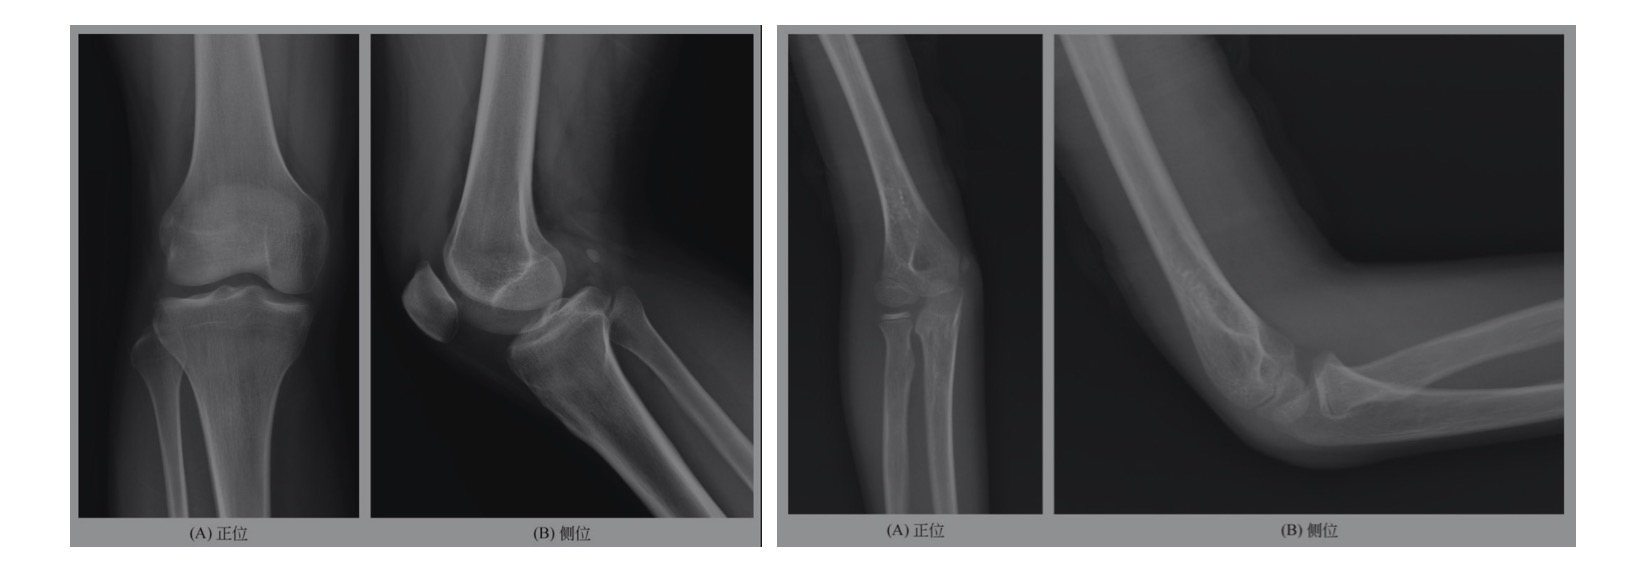

二、正常骨关节X线解剖及变异熟悉骨关节正常的X线解剖是骨肌系统疾病X线诊断的基础,而处于骨骼生长发育阶段的儿童,其正常骨骼表现与成人有所不同,应明确各部位骨化中心闭合的大致年龄,此外骨骼的生长变异较多,形态不一,如籽骨、副骨、骨嵴、血管沟、二次骨化中心不愈、邻近软组织结构牵拉及压迫等,有时与病变很难鉴别,必要时可加照对侧位并结合临床体征。正常成人骨关节见图5-1-

右膝关节组成各骨骨质形态、密度未见异常,骨骺及干骺端闭合,胫骨结节形态规则、愈合,关节面光整,关节间隙正常,周围软组织形态、密度未见异常。提示:用正位、侧位观察诸骨的骨质形态、密度及关节间隙有无异常;胫骨结节形态变异较多,必要时加照对侧对比;注意区别长骨血管沟及肌肉附着点的“拽曳”;软组织形态及密度改变对创伤有提示作用。

右肘关节组成各骨骨质形态、密度未见异常,桡骨小头及肱骨小头可见未闭合骨骺线,右肱骨内上髁可见骨骺影,关节面光整,关节间隙正常,周围软组织形态、密度未见异常。提示:应熟悉儿童正常骨骺大致闭合年龄。